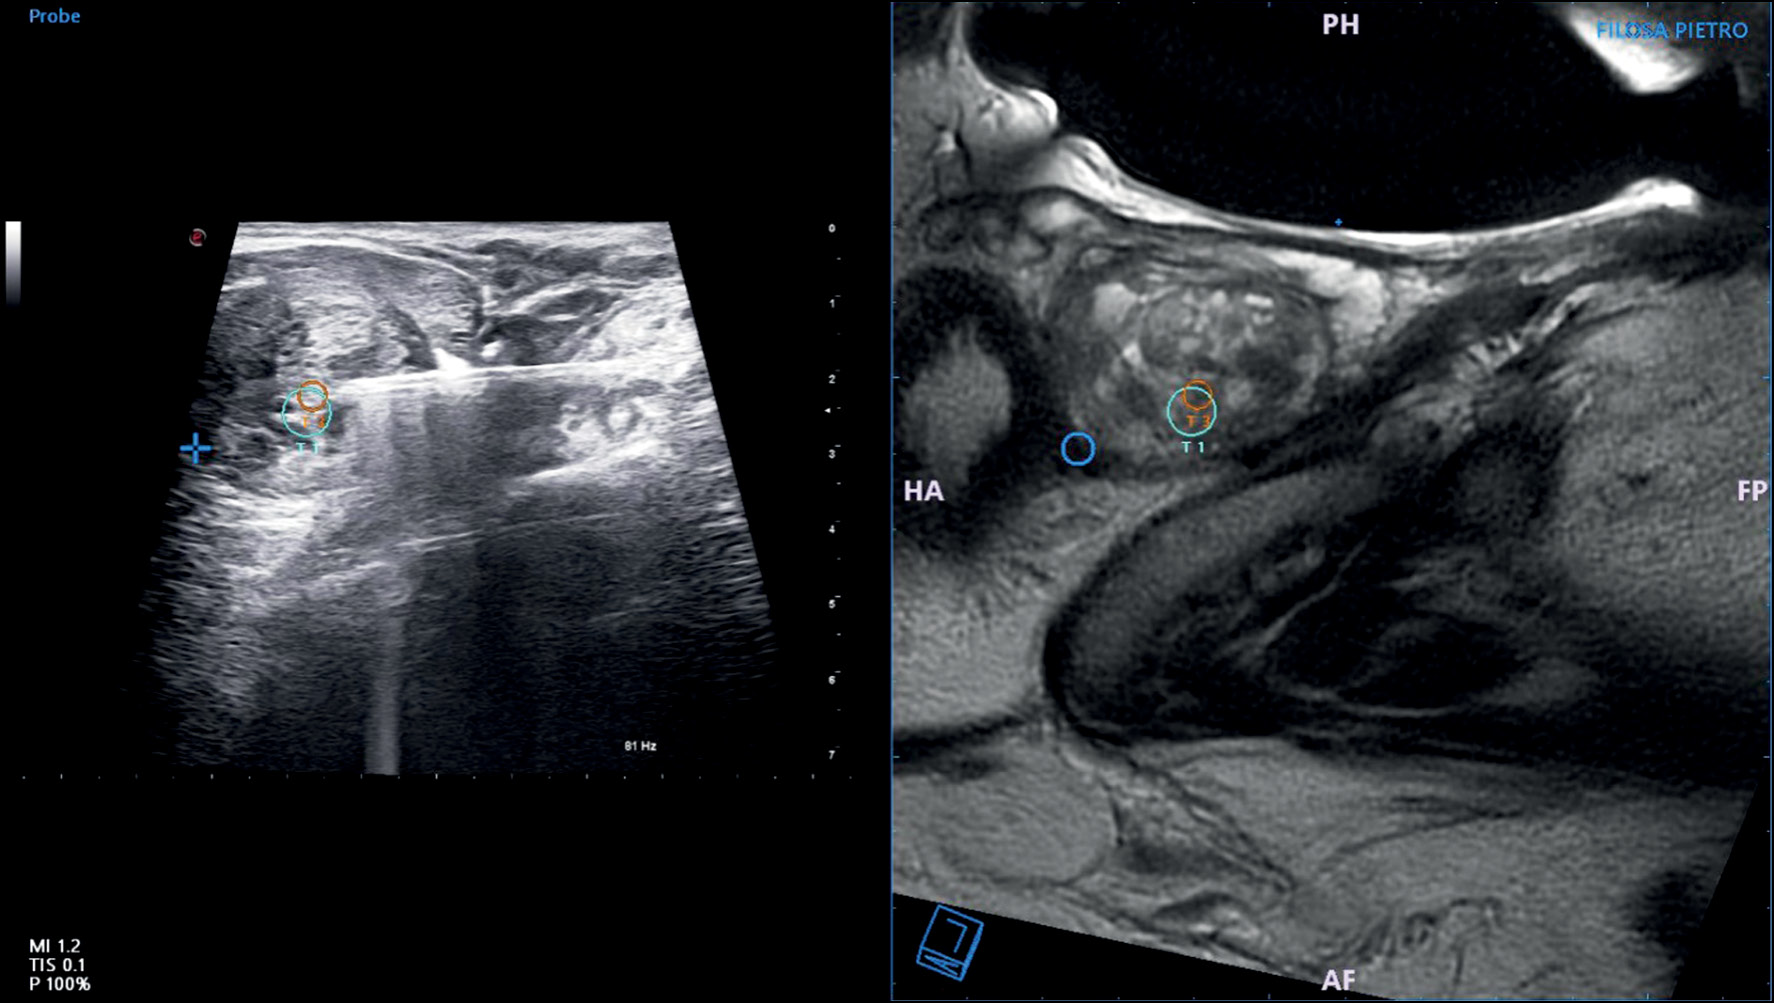

In this method, the operator images the prostate using US, as has been used for decades. While viewing the prostate, the MR images of that prostate, in which imaging was performed beforehand and images were stored in the device, are fused with real-time US images using a digital overlay, allowing the target(s) previously delineated by a radiologist to be brought into the US machine’s aiming mechanism. Fusion produces a three-dimensional (3D) reconstruction of the prostate, and the aiming and tracking of biopsy sites occur on the reconstructed model (Fig. 1 and 2) [25]. Several commercial platforms are now available, each with a different method of coregistration and a different hardware platform for lining up the biopsy with the coregistered picture [3]. Compared with VE, MRI–TRUS fusion-guided biopsy may have higher reproducibility because of less operator dependence and delivery of real-time feedback on actual biopsied areas [3]. The disadvantages include higher software/device costs, dependence on software for accuracy, and the associated learning curve and operator training [26] (Fig. 3 and 4).

Fig. 2. MRI–TRUS fusion-guided prostate biopsy. The prostate and lesions identified on MR images (in this case, on T2W imaging) are segmented. During the procedure, a 2D TRUS scan of the prostate was performed. Images were recorded semiautomatically. Co-viewing images can be tiled or overlaid. By merging the two images, the urologist can locate the lesion during a biopsy using real-time ultrasound guidance.

Fig. 4. Magnetic resonance imaging is fused with real-time TRUS using a digital overlay, allowing the target(s) previously delineated by a radiologist to be brought into the ultrasound machine’s aiming mechanism. Fusion enables the reconstruction of the prostate, and the aiming and tracking of biopsy sites occur on the reconstructed model.